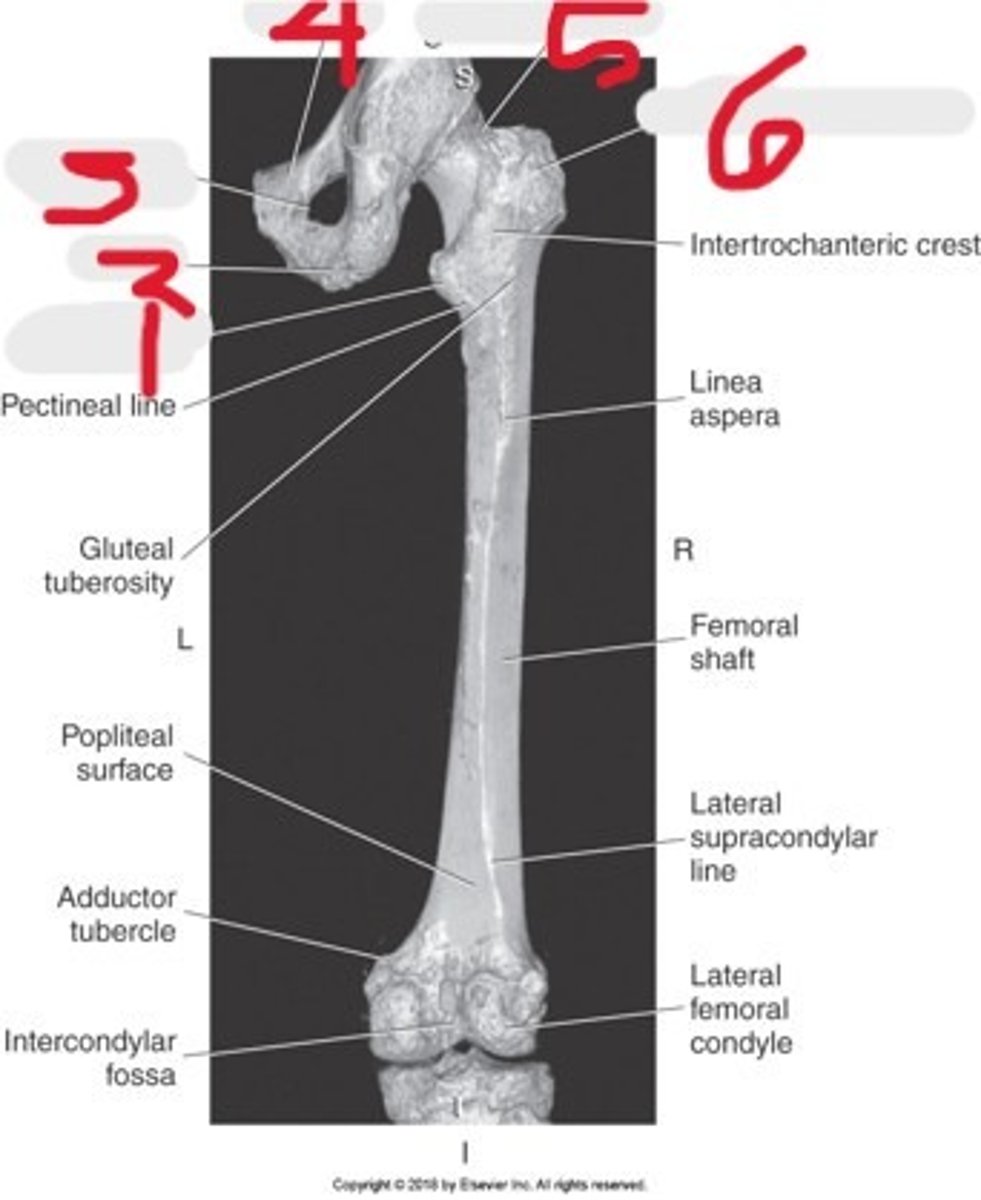

1) Ilium

2) Femoral neck

3) Greater trochanter

4) Lateral femoral condyle

5) Acetabulum

6) Femoral head

7) Femoral shift

8) Medial femoral condyle

Name all numbered structures